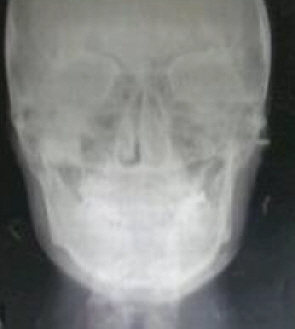

윗턱뼈돌출과치아윗앞니4개돌출,정중선삐뚦

제가치아교정을하려는이유는돌출되어서인더,상담을다니다보니 윗니가정중선이안맞고오른쪽으로틀어져있다고합니다. 글고제치아는 고르게난편인데 윗앞니4개가 앞으로약간더나왔으면서 윗턱뼈도돌출되었다합니다. 그러...